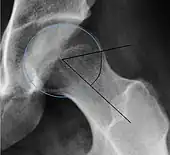

Projectional radiography ("X-ray")is often considered first line for FAI.[10] Anterior-posterior pelvis and a lateral image of the hip in question should be attained.[10] A 45-degree Dunn view is also recommended.[10][19]

| Alpha angle | ![]() |

Degree of bulging of the femoral head-neck junction: In normal conditions there is a symmetric concave contour at the junction of the femoral head and neck. Loss of this concavity or bone bulging may lead to cam type impingement. The degree of this deformity can be measured by the alpha angle. Although it can be measured in the cross-lateral view, the 45° Dunn view is considered more sensitive and the frog leg view more specific in determining pathologic values. |

|